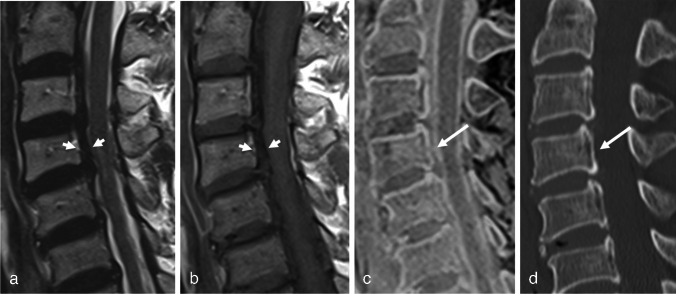

目的:比较三维快速低角度镜头(FLASH)与常规MRI序列对OPLL的诊断价值。材料和方法:本回顾性研究包括106例颈椎MRI和CT检查。OPLL组和对照组分别入组39例和67例患者。比较常规MRI使用涡轮自旋回波(TSE)和常规MRI加3D FLASH检测OPLL的诊断性能和读取器置信度。还计算了观察员间的一致意见。根据检测OPLL所需的序列,在OPLL组中定义了三个亚组(TSE组:仅通过检查TSE诊断为OPLL的病例;3D FLASH组:同时通过TSE和3D FLASH进行诊断的病例;无组:未经MRI诊断的病例)。比较各亚组间上pll的厚度。结果:常规MRI加入3D FLASH后,两种读卡器的诊断性能均有提高,其中读卡器2的差异有统计学意义(p = 0.006)。结论:3D FLASH与常规T1、t2加权成像相结合可有效检测OPLL。

Materials and methods: This retrospective study included 106 patients who underwent cervical spine MRI and CT. Thirty-nine and 67 patients were enrolled in the OPLL and control groups, respectively. Diagnostic performance and reader confidence for detecting OPLL were compared between conventional MRI using turbo spin echo (TSE) and conventional MRI plus 3D FLASH. Interobserver agreement was also calculated. Three subgroups were defined within the OPLL group according to the sequences required for detecting OPLL (TSE group: cases that were diagnosed as OPLL by reviewing only TSE; 3D FLASH group: cases that were diagnosed by reviewing both TSE and 3D FLASH; none group: cases that were not diagnosed on MRI). The thickness of the OPLL was compared between the subgroups.

Results: The diagnostic performance of both readers improved when 3D FLASH was added to conventional MRI, and the difference was statistically significant for reader 2 (p = 0.006). After adding 3D FLASH, reader confidence significantly increased (p < 0.001), and interobserver agreement improved from good to excellent. The three subgroups exhibited significantly different OPLL thicknesses (p = 0.008), with the thickest in the TSE group (4.5 mm), followed by the 3D FLASH (3.4 mm) and None groups (2.4 mm).

Conclusion: 3D FLASH can be helpful for detecting OPLL when combined with conventional T1- and T2-weighted imaging.